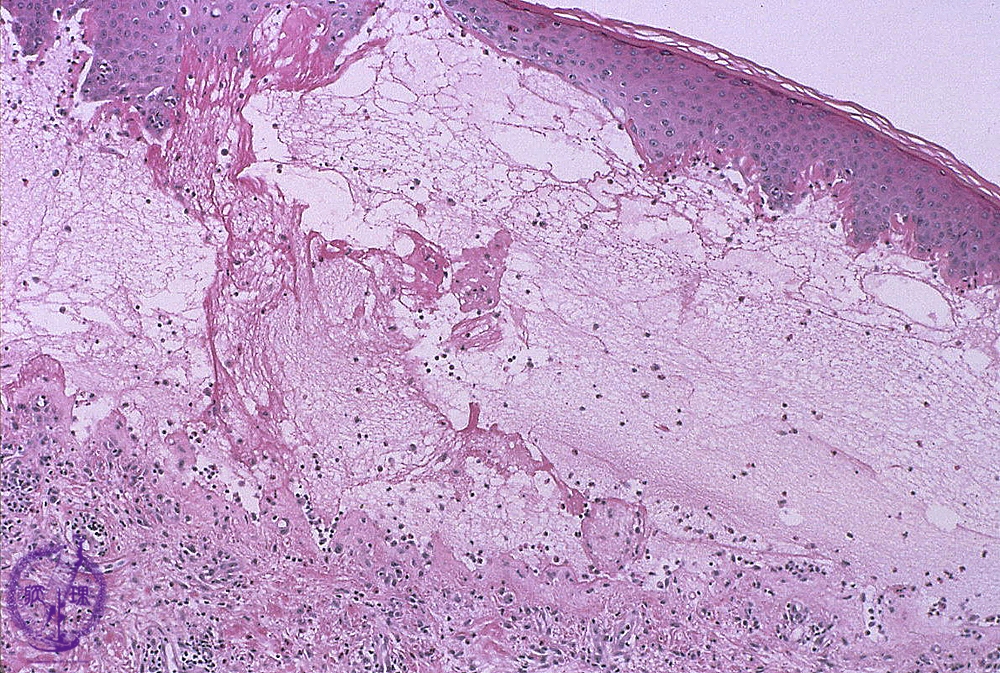

- ★(2)Vesiculobullous disease (Pemphigus vulgaris)

Microscopic image (Bullous pemphigoid): Fibrin deposition and numerous eosinophils are seen in the blister cavity. Eosinophil infiltration is also seen in the superficial dermis.